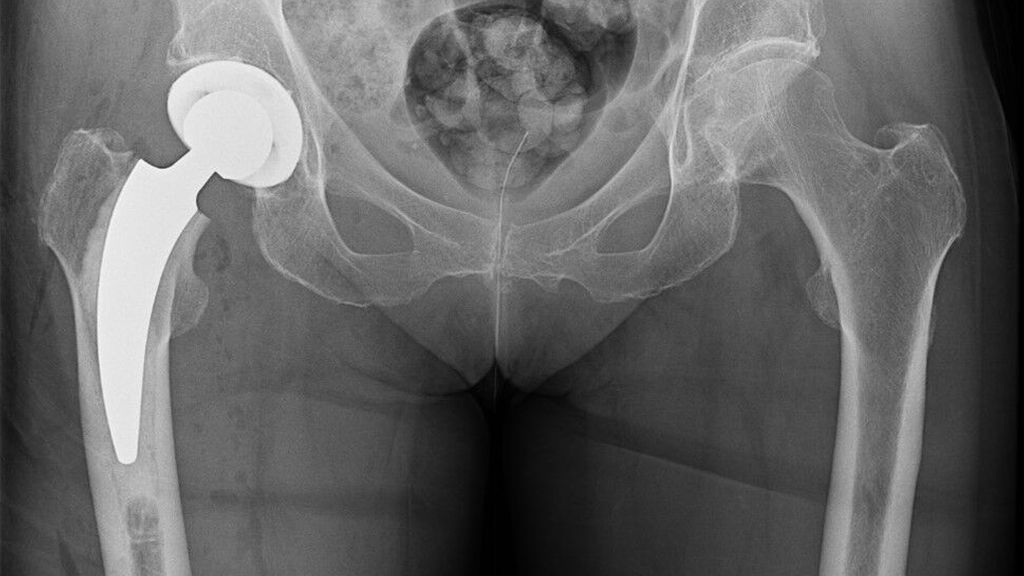

Die periprothetische Infektion (PPI) stellt eine der gefürchtetsten Komplikationen im Bereich der Orthopädie und Traumatologie dar. Sie ist verbunden mit hohen Morbiditäts- und ...

Mit zunehmendem Alter steigt die Rate an dislozierten medialen Schenkelhalsfrakturen. Meistens wird ein zementfreier oder zementierter Langschaft verwendet, seit Längerem werden auch ...